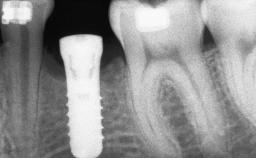

A 56-year-old woman presented for treatment with complete edentulism of the maxilla. She had been using a complete removable denture since she was relatively young (age 30). Her chief complaint at presentation was lack of retention of the upper denture and a desire for a better restoration in order to improve retention, function, and esthetics. An initial clinical examination showed that the anterior maxilla was moderately atrophic both horizontally and vertically, also revealing a vertical deficiency of the posterior alveolar process. The mandible included natural teeth from 45 to 35, with previous extrusion of the anterior teeth that was being orthodontically treated. Also, there were two external hexagon dental implants at sites 46 and 36 that had been inserted elsewhere at a previous point in time. As the conditions in the mandible were healthy, including the teeth and the two implants, the patient had no complaints there.

Bone Augmentation Horizontal|Sinus Floor Elevation|Staged

Augmentation Materials Autogenous chips|Autogenous block(s)

Bone Volume Deficient vertically or deficient vertically AND horizontally